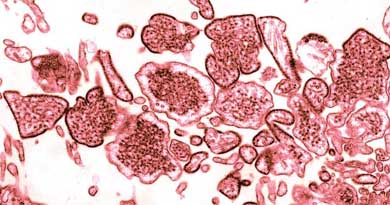

Nipah Virus (NIV) Infection

Nipah Virus infection is a newly emerging zoonotic disease causing severe illness and high fatality in animals and humans. Nipah virus was initially d...